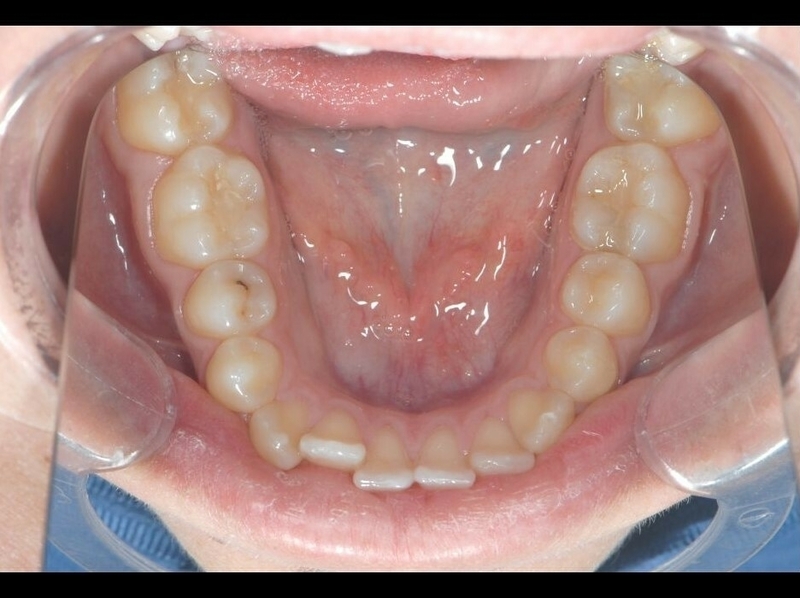

Cas 2 - Orthodontie par aligneurs invisibles

Avant

Après